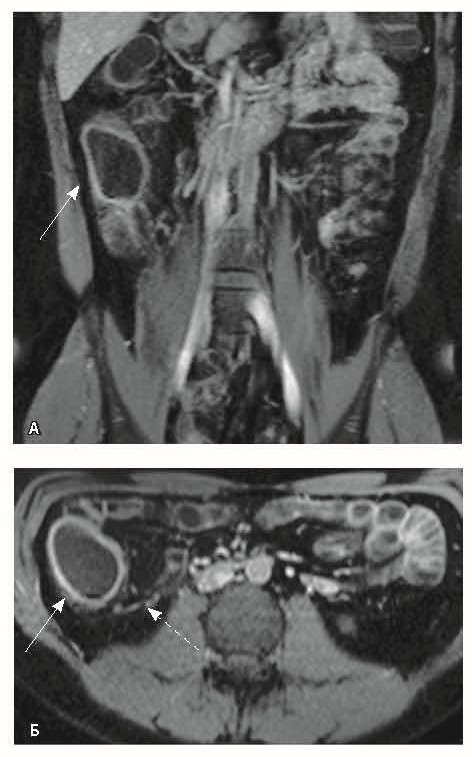

При мультиспиральной компьютерной томографии органов брюшной полости визуализировалась картина диффузного утолщения стенки толстой кишки с умеренным утолщением брыжейки и минимально выраженными явлениями лимфаденопатии в брыжейке (рис. 1).

Рис. 1. Мультиспиральная компьютерная томография органов брюшной полости с внутривенным введением контрастного вещества (йомепрол 350–100 мл), артериальная фаза: А – фронтальная проекция, Б – аксиальная проекция. Стрелками указано диффузное утолщение стенки толстой кишки и брыжейки